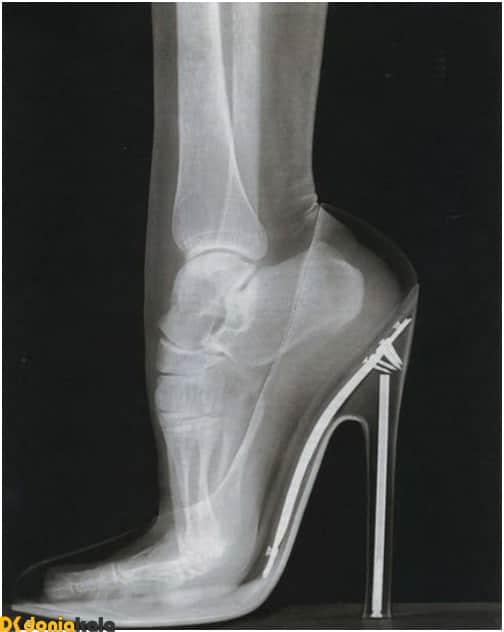

عوارض خطرناک پوشیدن کفش های پاشنه بلند

پوشیدن کفش های پاشنه بلند بر سلامت پاها تاثیر گذار است و استفاده از این کفش ها خطرات زیادی را برای خانم ها به همراه دارد، که این خطرات عبارتند از :

1.پوشیدن کفش هایی با پاشنه بلندتر از 7 سانتی متر روی زانوها فشار زیادی وارد می کند و احتمال ابتلا به آرتروز را بیشتر می کند.

2.پوشیدن کفش پاشنه بلند سبب پیچ خوردگی مچ پا به سمت بیرون و در نتیجه موجب رگ به رگ شدن شدید رباط پا می شود و به همین علت خطر ابتلا به آرتروز افزایش می یابد.

3.پوشیدن کفش پاشنه بلند روی مفصل انگشت شست پا فشار وارد می کند و این فشار از مفصل استخوان متاتارس به استخوان نخودی شکل انگشت پا منتقل می شود و در نهایت این فشار وارد شده به استخوان یا اعصاب موجب التهاب آن می شود.

عوارض دیگری که هنگام پوشیدن کفش پاشنه دار در پا ایجاد می شود :

- انحراف انگشت شست پا

- میخچه

- تاول انگشتان

- خمیدگی انگشتان

- دردهای مزمن کمر

- دردهای مفاصل

- درد زانو

- درد پاشنه پا

- خستگی های زودرس